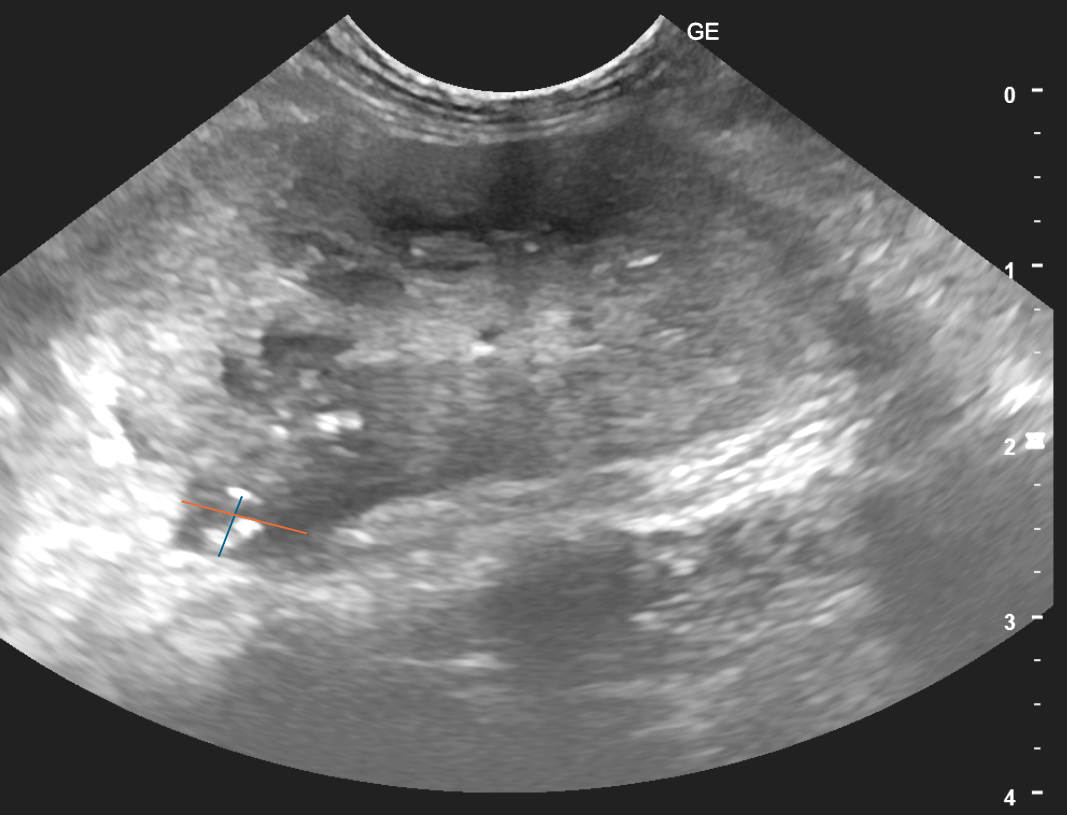

よって、腫瘤に直接針を刺し腫瘍細胞を採材する「針生検(FNA)」を実施します。

採材した細胞を、顕微鏡下にて診断します。

院内での診断が困難な場合、病理検査医へ外注検査を依頼することもあります。

超音波ガイド下FNA